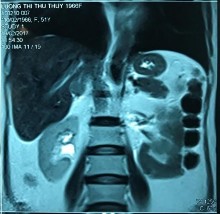

Phim MRI và bệnh phẩm bướu tuyến vỏ thượng thận bên phải

[BN Lương Thị Thu T., 51 tuổi, SNV: 2170021376]

Bệnh nhân hội chứng Cushing do bướu TTT

[Lương Thị Thu T., 51 tuổi, SNV: 2170021376]

Ghi chú: hình bên trái: trước phẫu thuật; hình bên phải: sau phẫu thuật 08 tuần, triệu chứng có cải thiện sau 08 tuần phẫu thuật